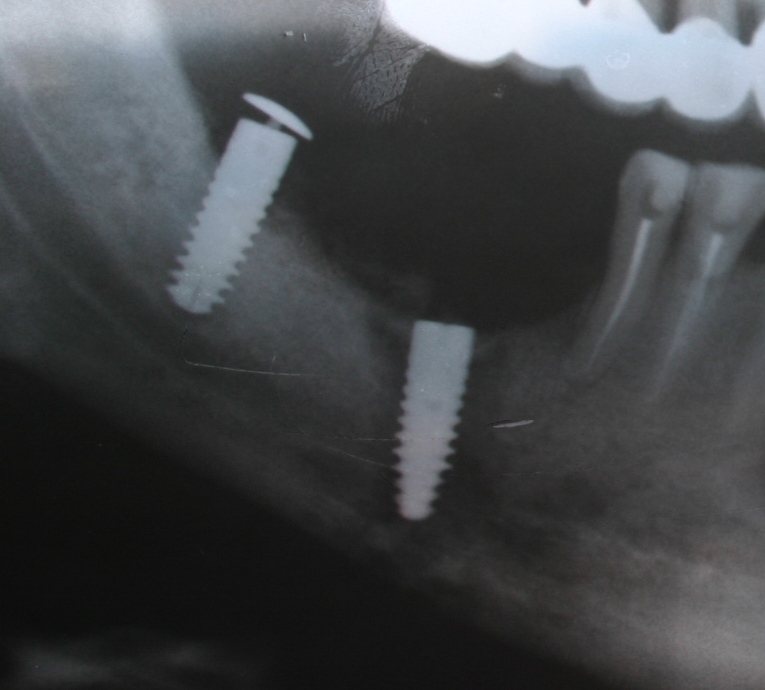

Исследование на рентгене после имплантации зубов

Раздел: Снимки-откровения